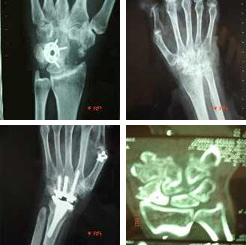

Artrosis intercarpianas

Las artrosis del carpo o intercarpianas son mucho más frecuentes de lo que en principio puede imaginarse. Son debidas habitualmente a secuelas de traumatismos y raramente debido a problemas degenerativos puros. Otro origen habitual de problemas artrósicos en la muñeca es el derivado de las artritis evolucionadas de cualquier origen, sobre todo como consecuencia de lesiones inflamatorias crónicas.

Las más habituales son debido a lesiones de antiguas fracturas mal curadas o que han pasado desapercibidas como son el caso de las fracturas de escafoides. Una vez evolucionadas se pueden solucionar con artrodesis intercarpianas o prótesis totales de muñeca.